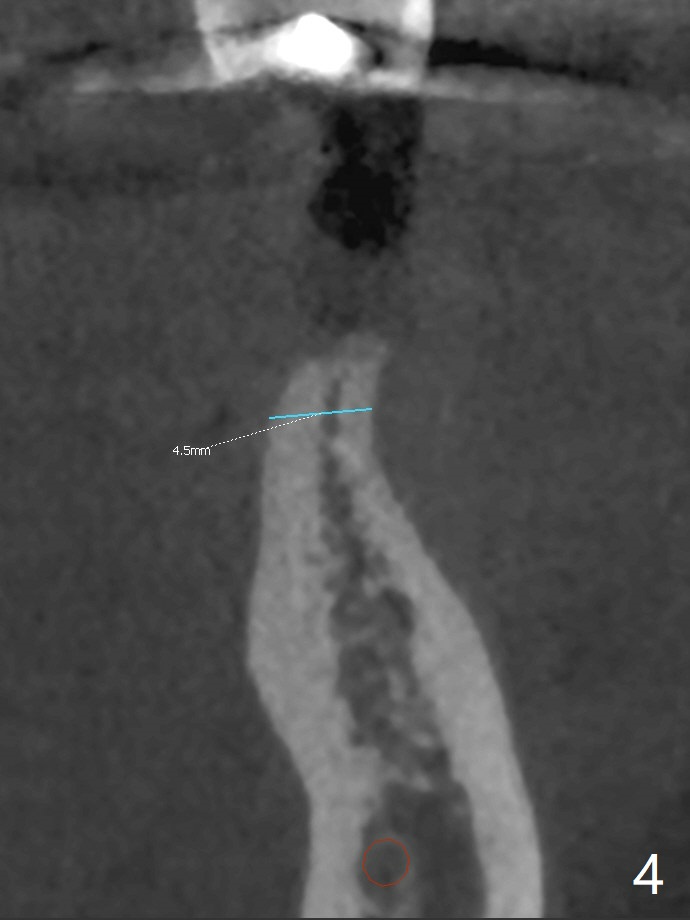

A 51-year-old woman has discomfort with #18-20 overcontoured FPD.  CT, taken after removal of the FPD, shows the narrow space and narrow ridge.  A 3.5 mm 2-piece (Fig.1) or 3.0 mm 1-piece (Fig.2,3) implant is indicated.  For ridge split, the ridge top will be trimmed with surgical handpiece and round bur (Fig.4).